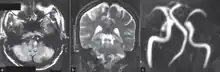

a)High signal in left postero lateral indicates a infarct and thrombosed left vertebral artery b) infarct (circle ) c)indicates absence of normal left vertebral artery ( circle )